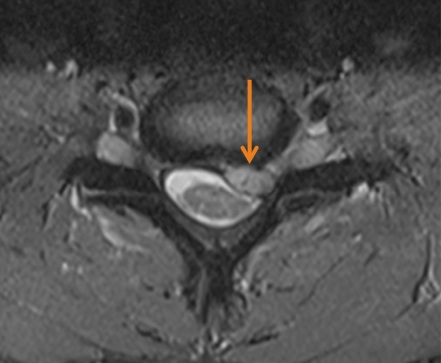

Kernspintomographie (MRT): Knöcherne Stenose in der Halswirbelsäule

Kernspintomographie (MRT): Degeneration der Bandscheibe C5/C6